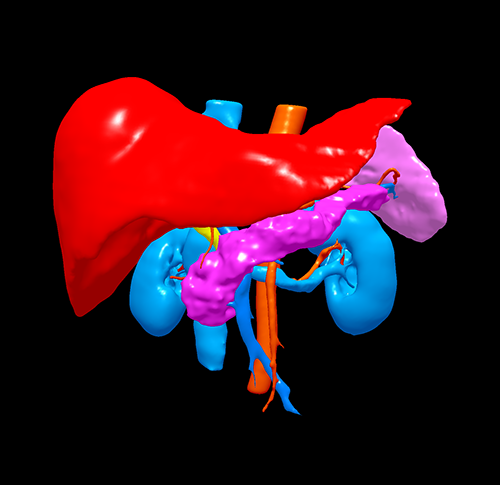

胰头腺癌---胰十二指肠切除